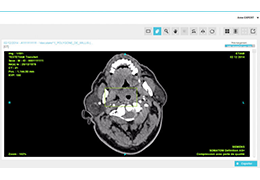

Visualization Tools

Parametric and non-parametric statistical maps may be superimposed both on the original functional scans as well as onto T1-weighted 2D or 3D anatomical reference scans. Time courses of selected regions-of-interest (ROIs) are available both in 2D and 3D representations. Statistical maps may be computed either in the 2D or 3D representation since structural as well as functional 4D data (space x time) are transformed into Talairach space. This allows you to compare activated brain regions across different experiments and across different subjects